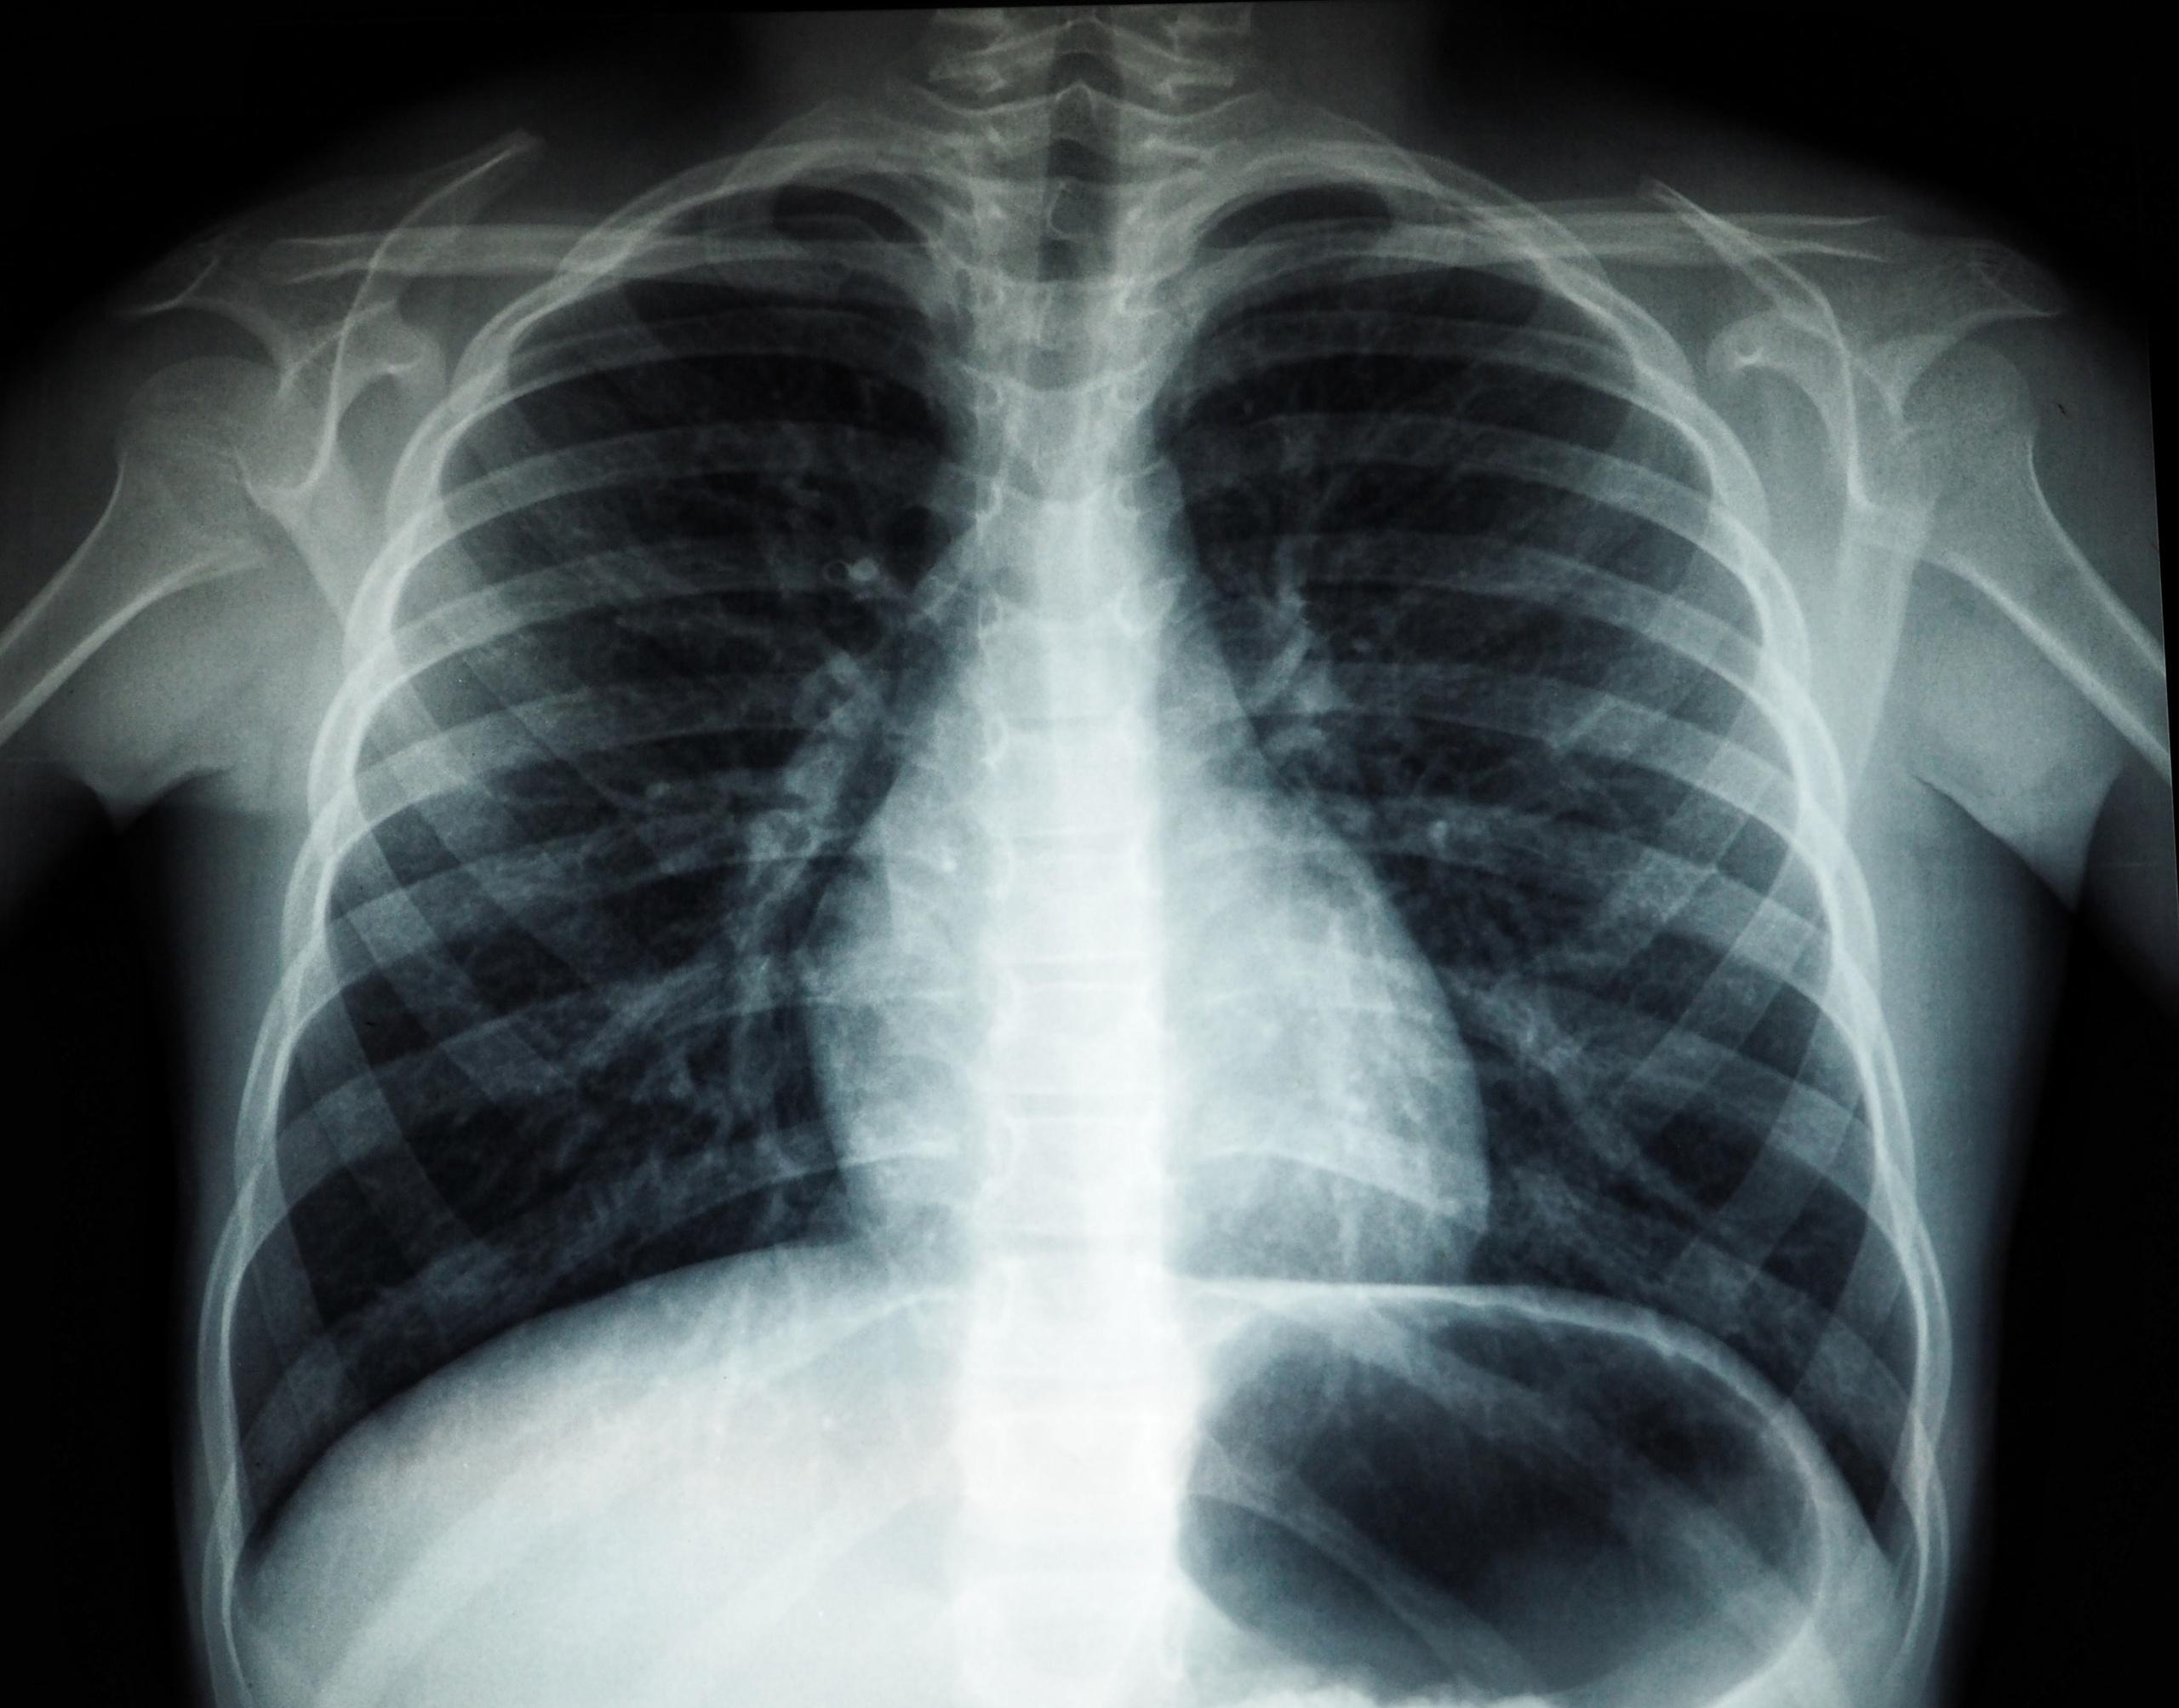

36-летний житель Красноярского района Самарской области стоит на учете в наркологическом диспансере и обязан проходить флюорографию. Однако в добровольном порядке мужчина от прохождения обследования отказывался. Пройти медицинский осмотр в обязательном порядке его заставил суд.

После этого мужчина решил все же пройти обследование и отнес снимок легких в медицинское учреждение.

Ранее также через суд обязали сделать флюорографию жителя Самары. Он знал, что должен проходить обследование не реже двух раз в год, поскольку состоял на туберкулезном учете.